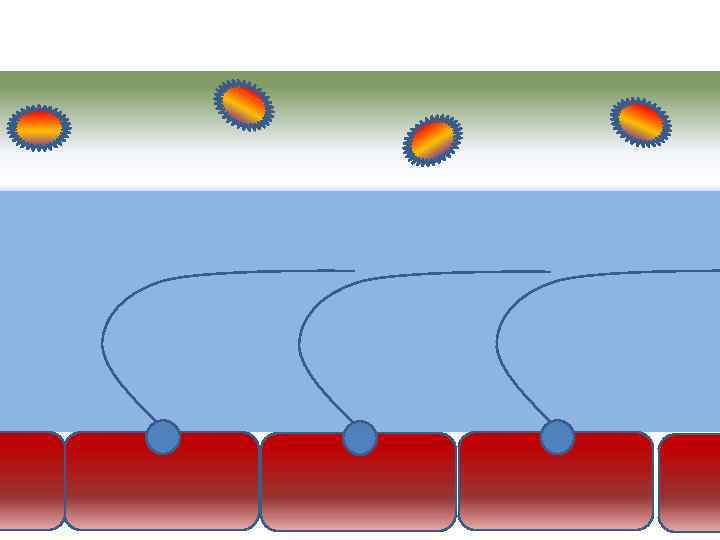

Движение клеток реснитчатого эпителия Движение вперед 1 – 3 Обратное движение 4 – 8

Движение клеток реснитчатого эпителия Движение вперед 1 – 3 Обратное движение 4 – 8

Оптимальное увлажнение Достаточная продукция слизи Хороший транспорт Экономит энергию и воду Защитная функция

Оптимальное увлажнение Достаточная продукция слизи Хороший транспорт Экономит энергию и воду Защитная функция

Механизм защиты легкого Слизь (зеленый цвет) нейтрализует и связывает патогенную флору(синий цвет) Слизь – это барьер между клетками и патогенной флорой Слизь – это транспортное средство

Механизм защиты легкого Слизь (зеленый цвет) нейтрализует и связывает патогенную флору(синий цвет) Слизь – это барьер между клетками и патогенной флорой Слизь – это транспортное средство

Плохое увлажнение • Вязкая слизь - потеря ресничек • Высушивание слизистой смерть клеток • Высушивание слизи в бронхиолах-ателектазы • Затраты энергии на согревание воздуха • Затраты воды на увлажнение

Плохое увлажнение • Вязкая слизь - потеря ресничек • Высушивание слизистой смерть клеток • Высушивание слизи в бронхиолах-ателектазы • Затраты энергии на согревание воздуха • Затраты воды на увлажнение